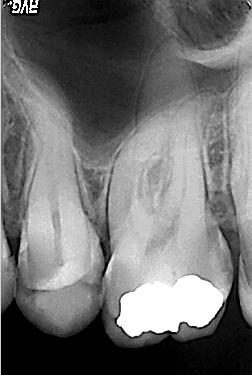

Röntgenologischer Ausgangsbefund

Röntgenologischer Ausgangsbefund im August 2003 bei Zahn 16 mit apikaler Parodontits an der palatinalen Wurzel. Der eingeführte Guttaperchastift korrespondiert mit der distobuccalen Wurzelspitze

Distalexzentische Projektion

Distalexzentische Projektion mit zweitem Parodontalspalt in der mesiobuccalen Wurzel als deutlicher Hinweis für ein zusätzliches viertes Kanalsystem